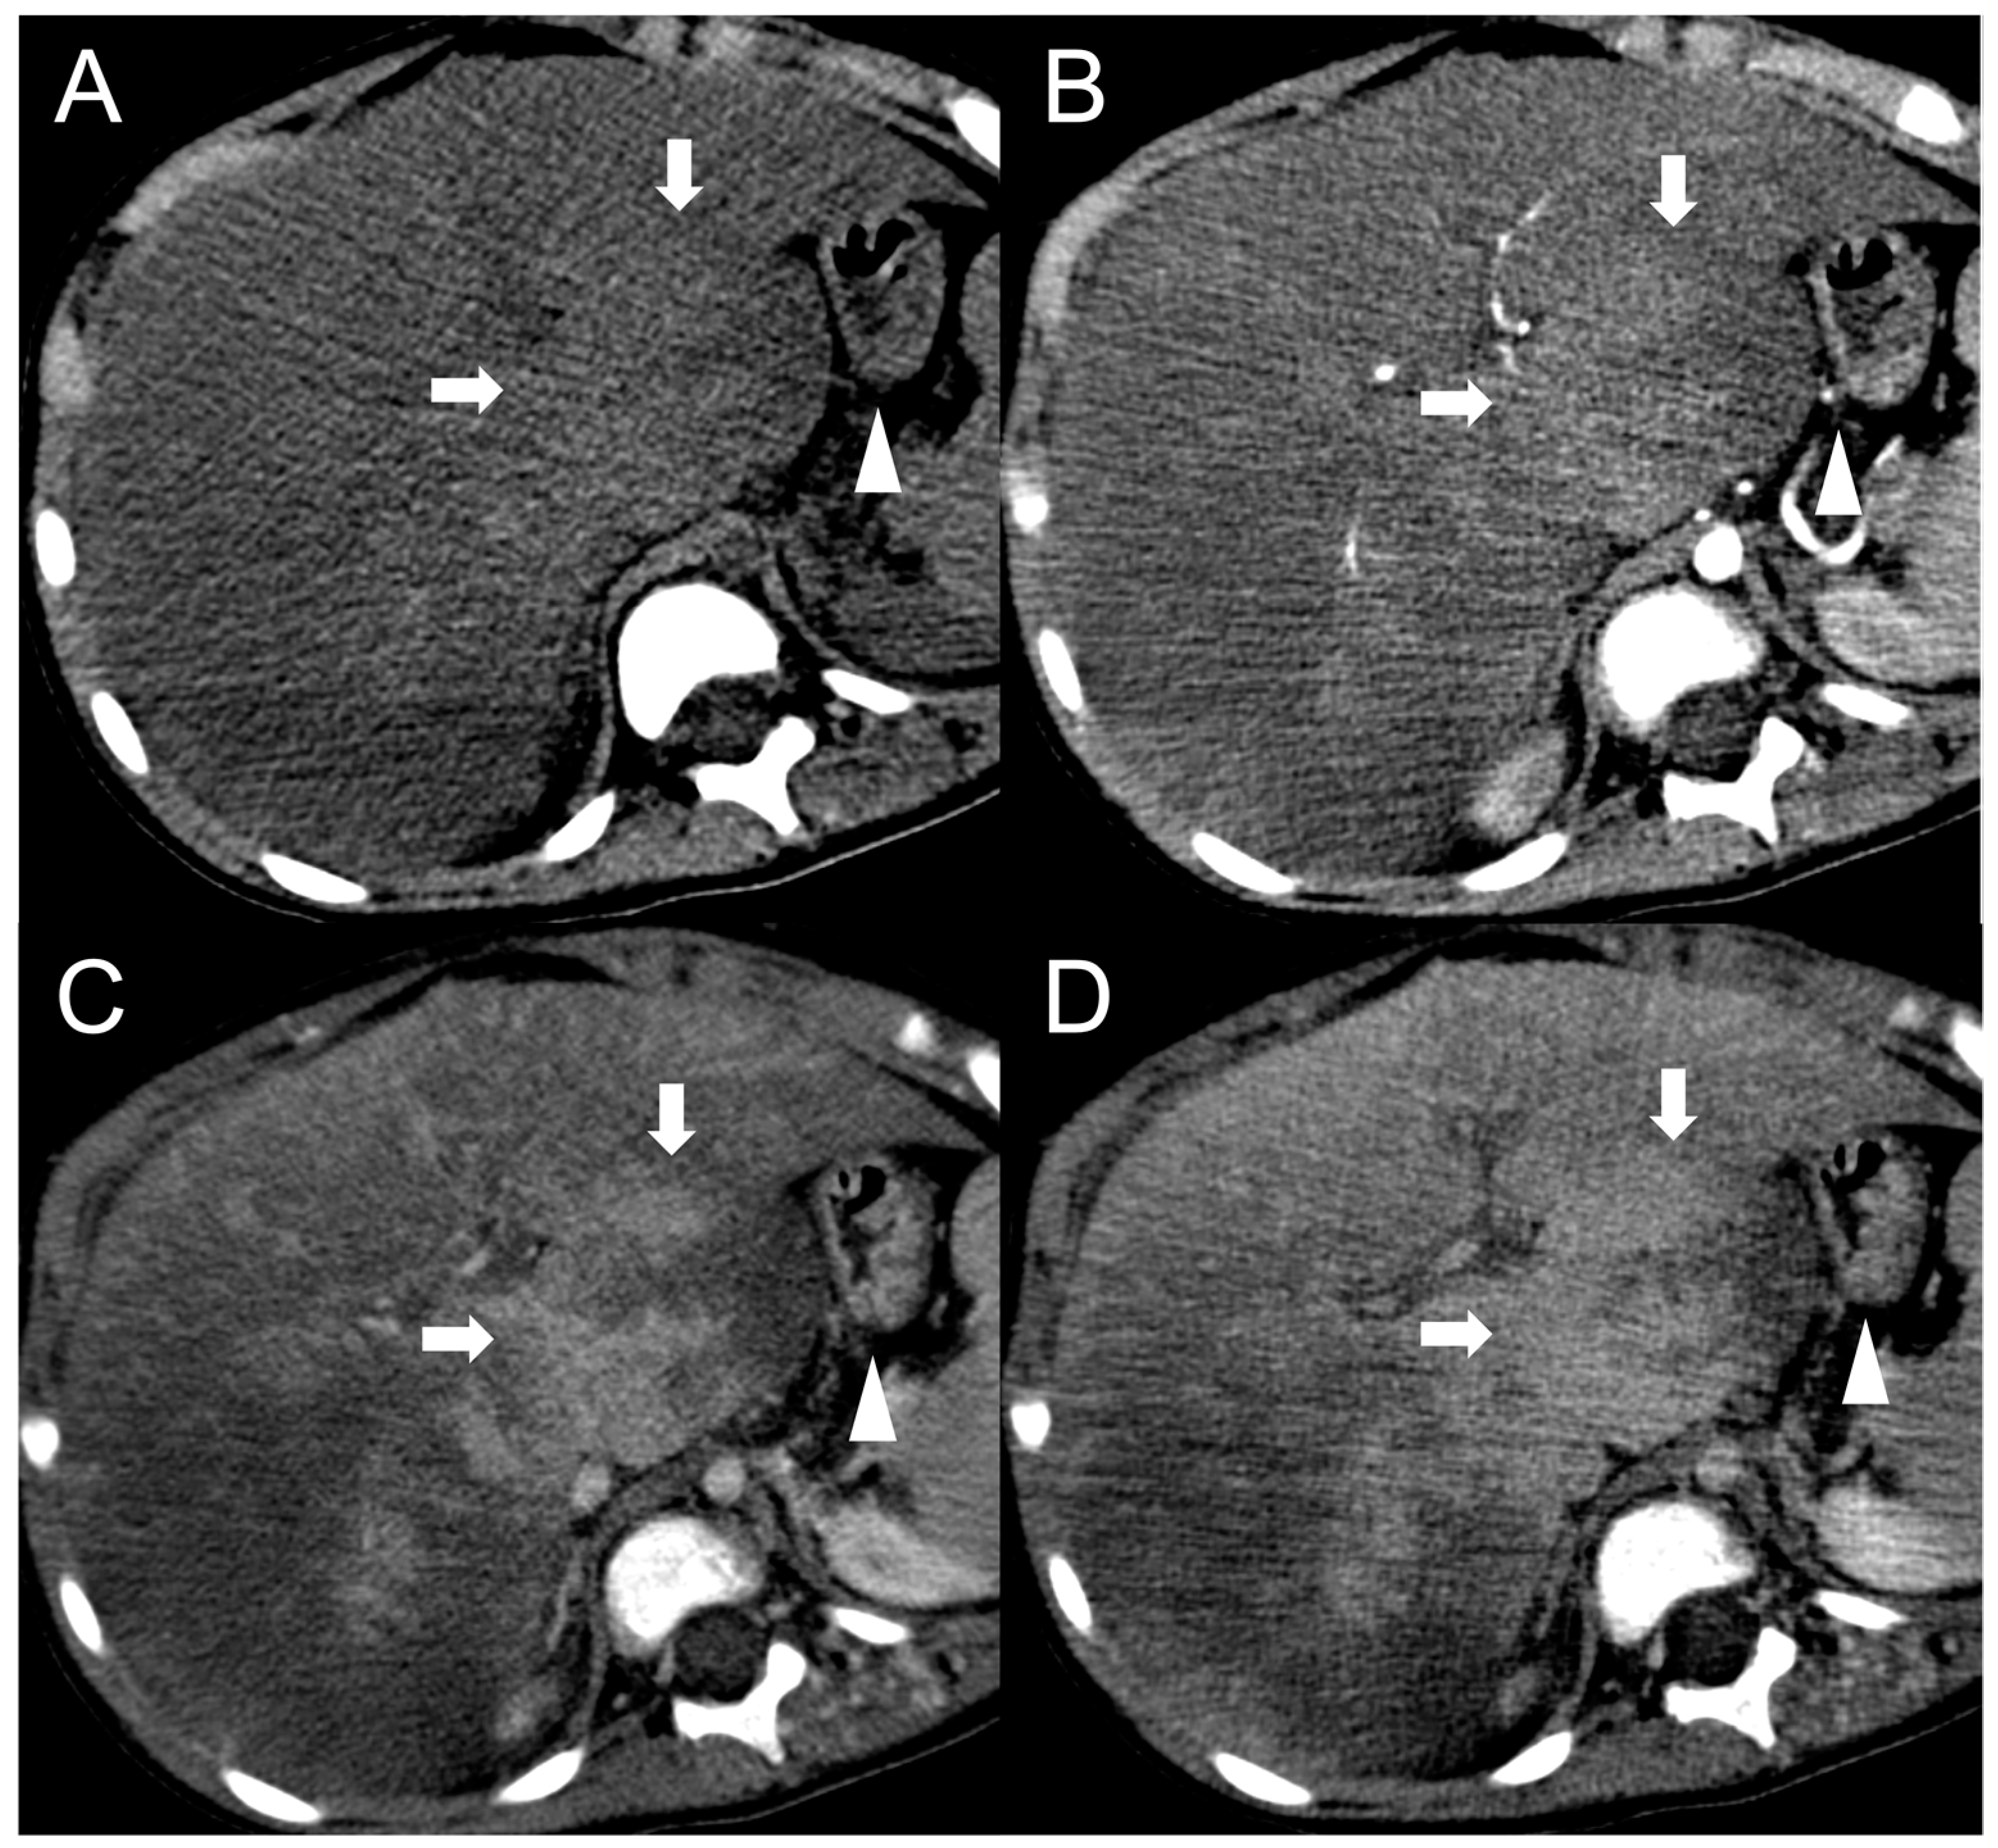

The presence of a central scar is another common finding in FNH-like RNs, particularly in those larger than 1 cm [10]. This scar typically appears as a hypointense, central stellate area on fat-suppressed T1-weighted imaging and a hyperintense area on T2-weighted imaging (Figure 2). Moreover, since regenerative nodules are made up of normal hepatocytes, they appear isointense or slightly hyperintense to the adjacent liver parenchyma on diffusion-weighted imaging, and there is no significant reduction in the diffusion values observed on the ADC map. These characteristics help to differentiate between regenerative and HCC nodules with reasonable confidence in patients with BCS.

Figure 2.

FNH-like RN with central scar (arrow) in a 34-year-old male patient with Budd–Chiari syndrome. In MRI, the scar is typically hyperintense on fat-saturated T2-weighted images (A) and hypointense in T1-weighted images (B). In the arterial phase after contrast agent administration, the scar can be identified as a central stellate area that appears hypodense in CT (C) and hypointense in MRI (D). In the CT delayed phase, the nodule shows increased density, but a central hypodense component representing the scar remains visible (E). In gradient-echo T1-weighted images acquired in the hepatobiliary phase (F), the scar is clearly depicted as a central low-signal area.